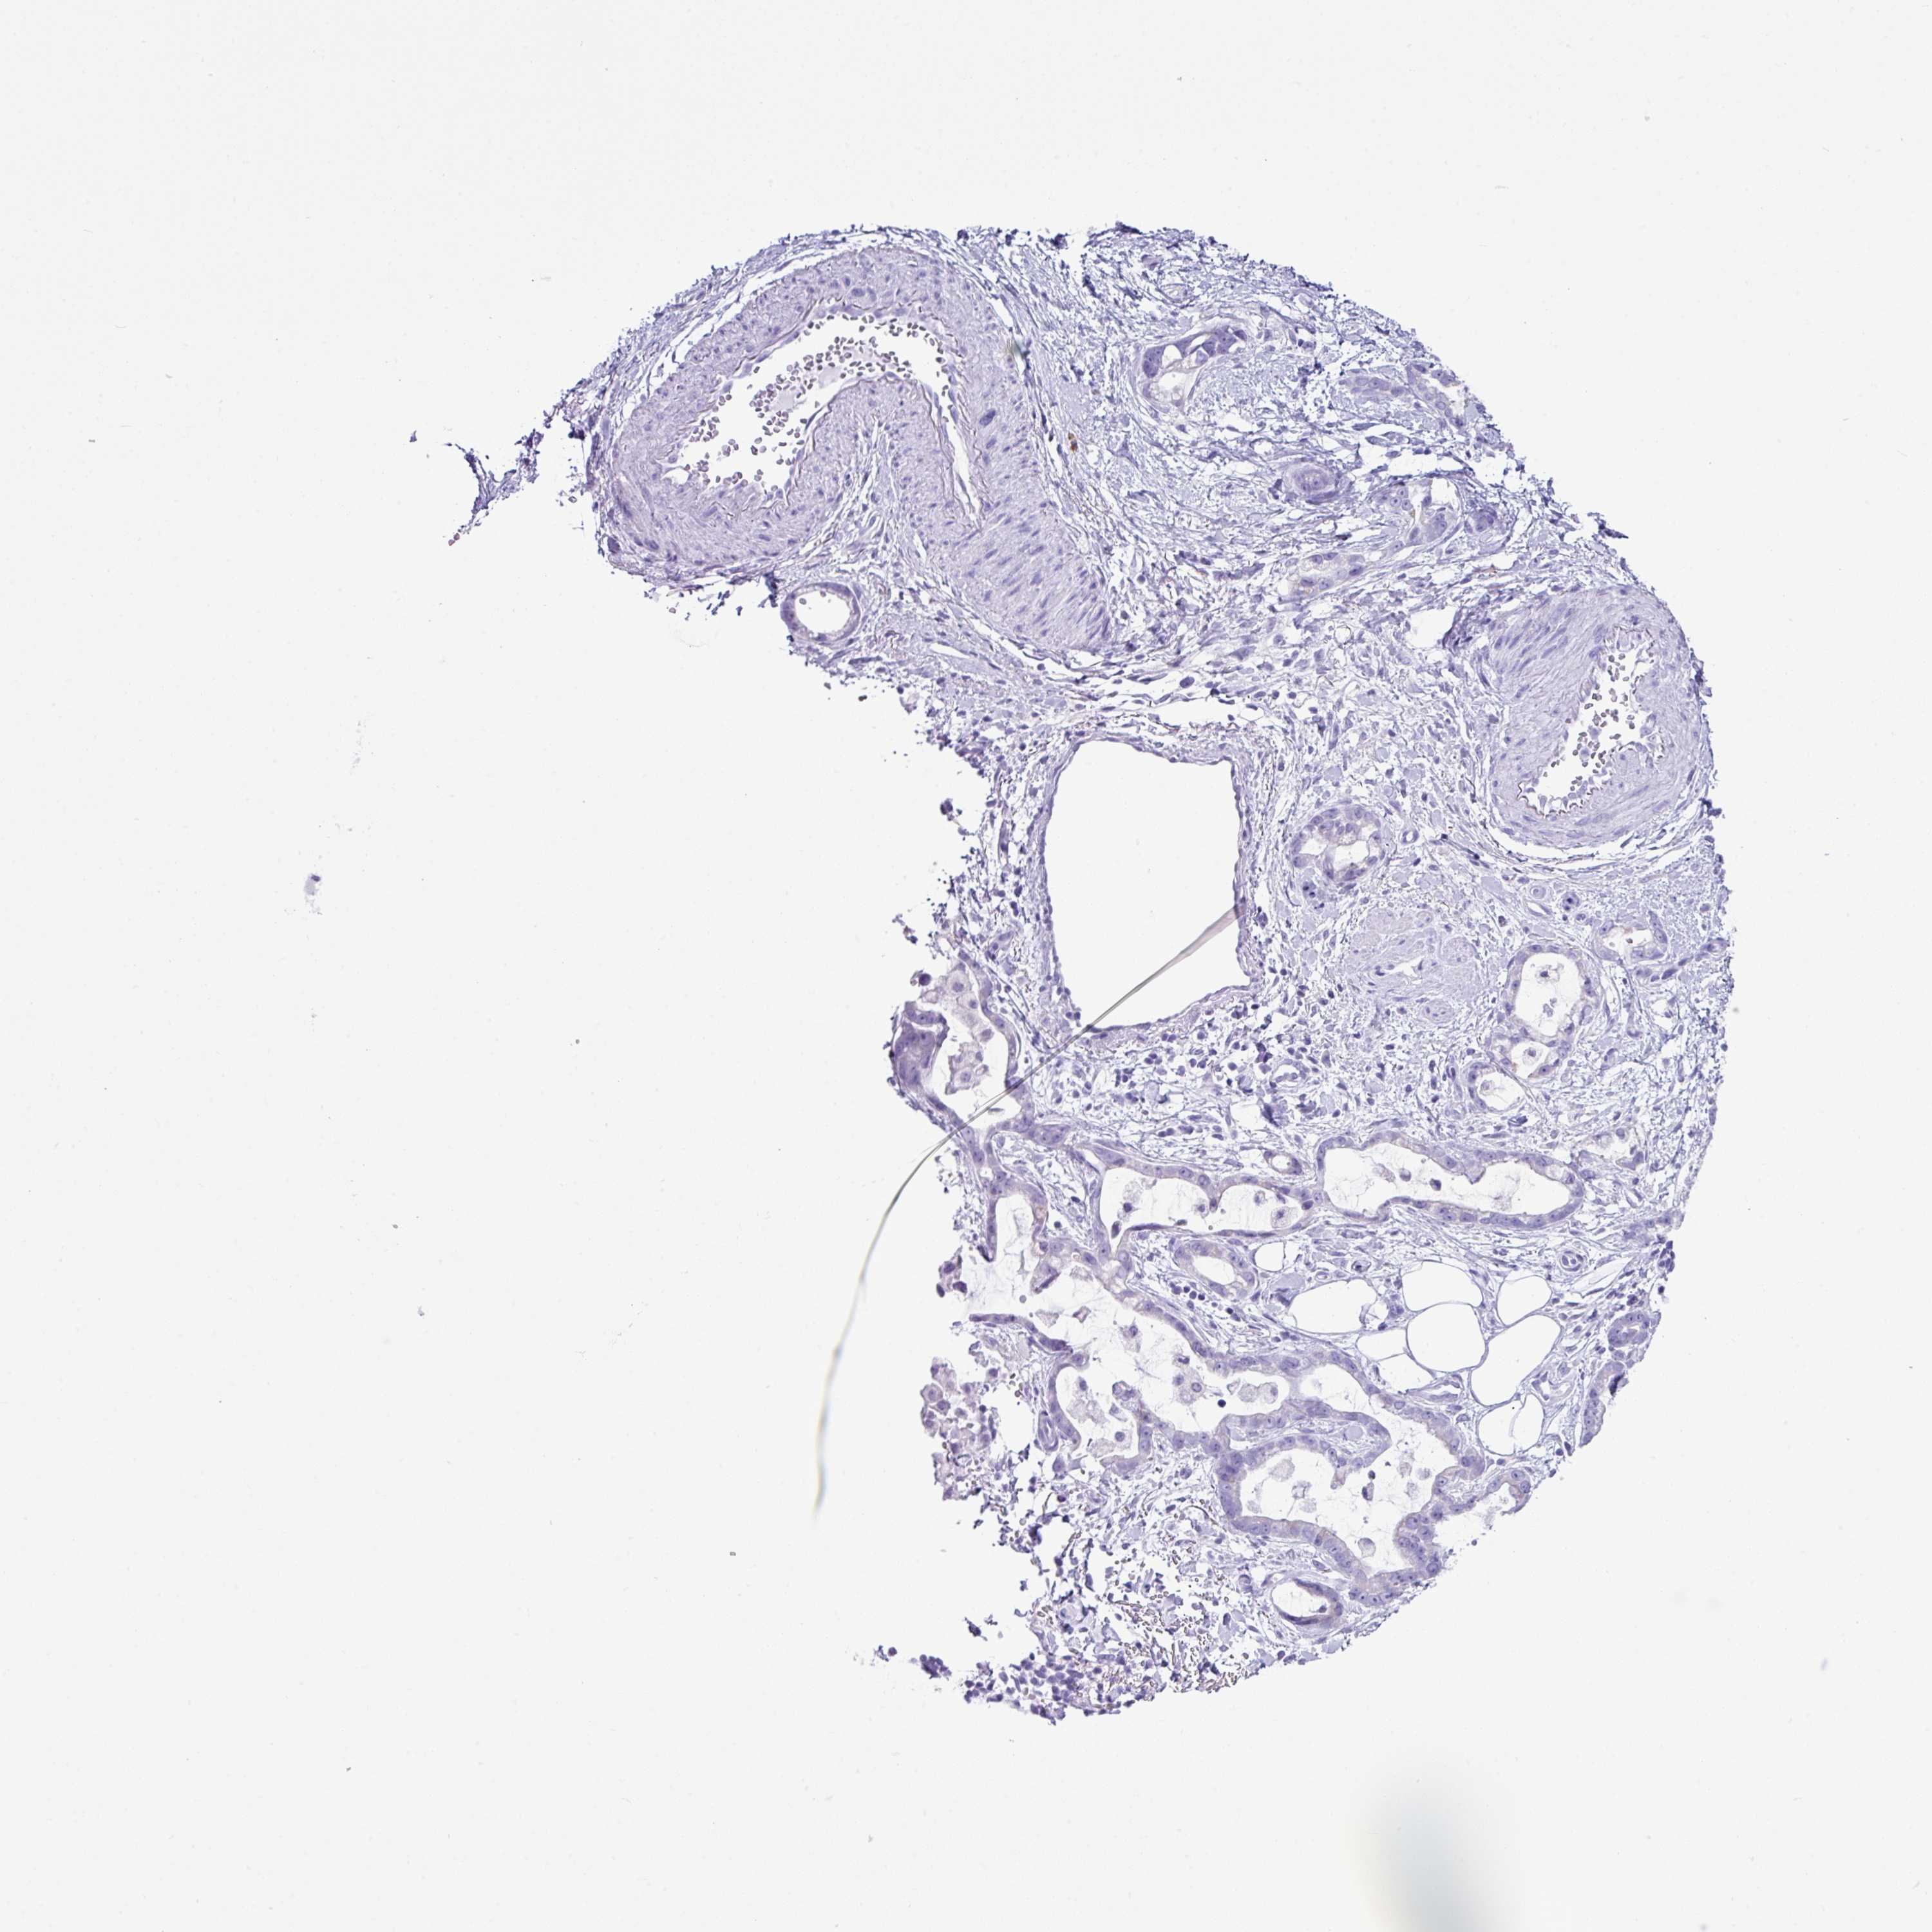

STOMACH CANCER - Protein expressioni

A mouse-over function shows sample information and annotation data. Click on an image to view it in a full screen mode. Samples can be filtered based on level of antibody staining by selecting one or several of the following categories: high, medium, low and not detected. The assay and annotation is described here.

Note that samples used for immunohistochemistry by the Human Protein Atlas do not correspond to samples in the TCGA dataset.

Antibody stainingi

Antibody staining in the annotated cell types in the current human tissue is reported as not detected, low, medium, or high, based on conventional immunohistochemistry profiling in selected tissues. This score is based on the combination of the staining intensity and fraction of stained cells.

Each image is clickable and will lead to virtual microscopy that enables deeper exploration of all samples and also displays staining intensity scores, fraction scores and subcellular localization as well as patient and tissue information for each sample.

Antibody HPA052843

Staining

High

Medium

Low

Not detected

Intensity

Strong

Moderate

Weak

Negative

Quantity

>75%

75%-25%

<25%

None

Location

Nuclear

Cytoplasmic/membranous

Cytoplasmic/membranous,nuclear

Adenocarcinoma, NOS